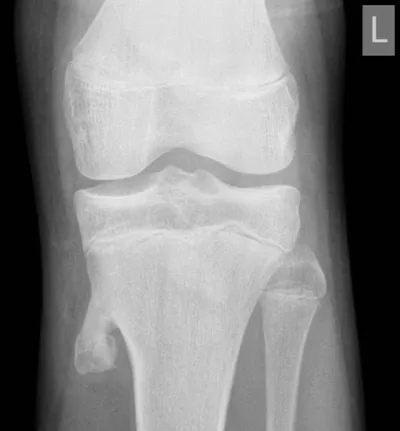

Osteochondroma Radiology Images

This collection contains 1 radiology images related to osteochondroma, including various imaging modalities such as X-rays, MRIs, CT scans, and ultrasound images commonly used in medical diagnosis and education.